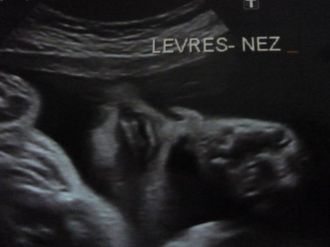

2 eme EchoLa meilleure de toute, tout va bien elle etait tranquille les jambes croisées c'etait trop drole.

Apparrament toutes les mesures sont bonnes, vivement qu'elle soit dans mes bras, encore quelques mois a attendre !!!!  Message déposé le 23.11.2011 à 17:59 - Commentaires (0)